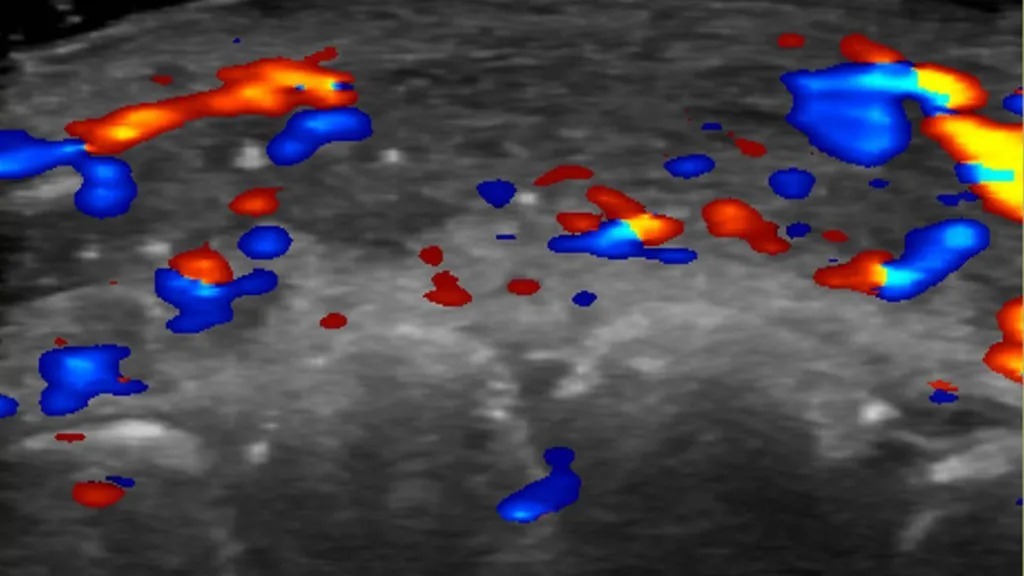

სპეციალისტებმა ულტრაბგერითი ტექნოლოგიის მეშვეობით არასასურველი შედეგის მქონე ინიექციის 100 შემთხვევა შეისწავლეს. ისინი კლინიკებს სწორედ ულტრაბგერითი ანალიზის ჩატარებას ურჩევენ, სანამ კანში ამოსავსებ ნივთიერებას შეიყვანენ. ამით ახლომდებარე არტერიებში სისხლის მიმოქცევის შეფერხება შეიძლება ავიცილოთ თავიდან.

მეცნიერთა კვლევამ აჩვენა, რომ გაანალიზებული შემთხვევების თითქმის ნახევარში სისხლი არ მიედინებოდა მომცრო სისხლძარღვებში, რომლებიც ზედაპირულ არტერიებს უფრო ღრმა არტერიებთან აკავშირებს; შემთხვევების მესამედში მიმოქცევის დარღვევა შენიშნეს მთავარ სისხლძარღვებშიც.

სწორედ ამის თავიდან ასაცილებლად გვირჩევენ ინიექციამდე ულტრაბგერითი კვლევის ჩატარებას, რათა ნივთიერება არტერიებთან ზედმეტად ახლოს არ დაგროვდეს. გართულებებისას იმავე მეთოდითაა შესაძლებელი იმ ადგილის პოვნაც, რომელიც მკურნალობას საჭიროებს.